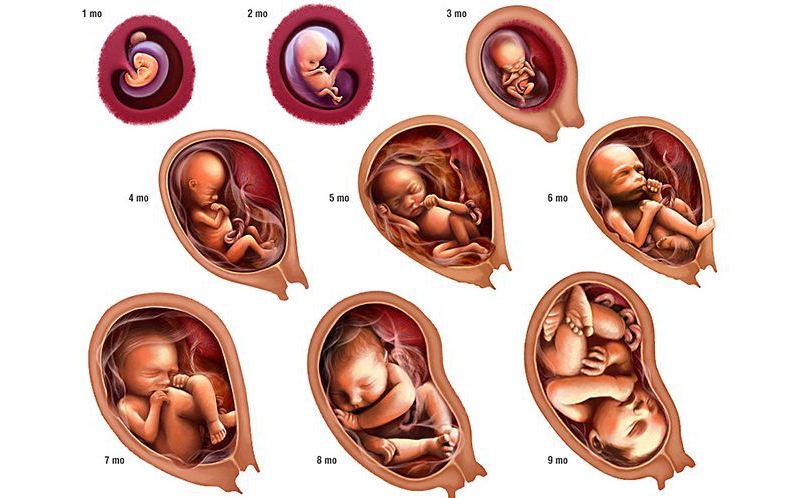

The Ayurvedic Approach to Fetal Development: Nurturing Life Month by Month (Garbhavrudhhi) Pregnancy is one of the most sacred and…

From the moment of conception, Ayurveda views pregnancy not just as a biological process, but as a sacred union of…